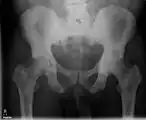

X-ray: Bone cancer in hip, spread from prostate cancer. -

X-ray: Bone cancer in hip, spread from breast cancer.